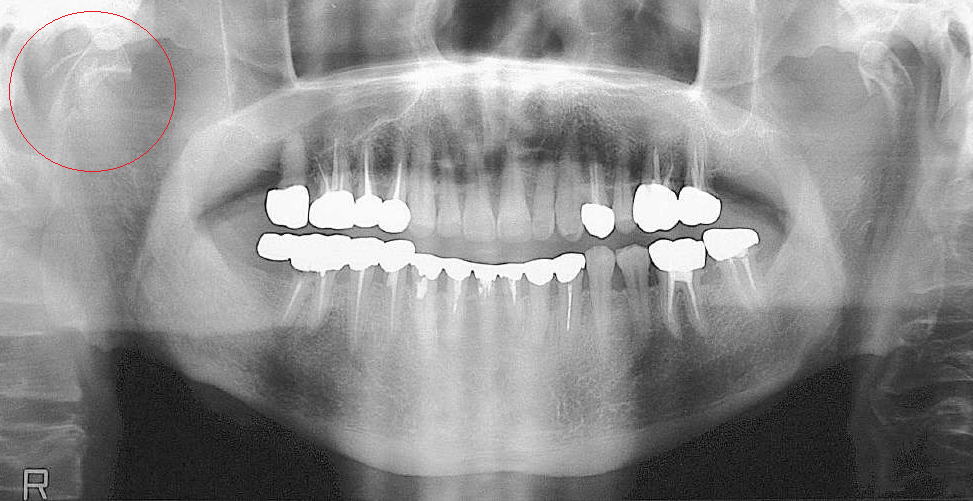

症例1:右関節頭の骨折

咬合の変位が少ない場合には保存療法が選択されます。